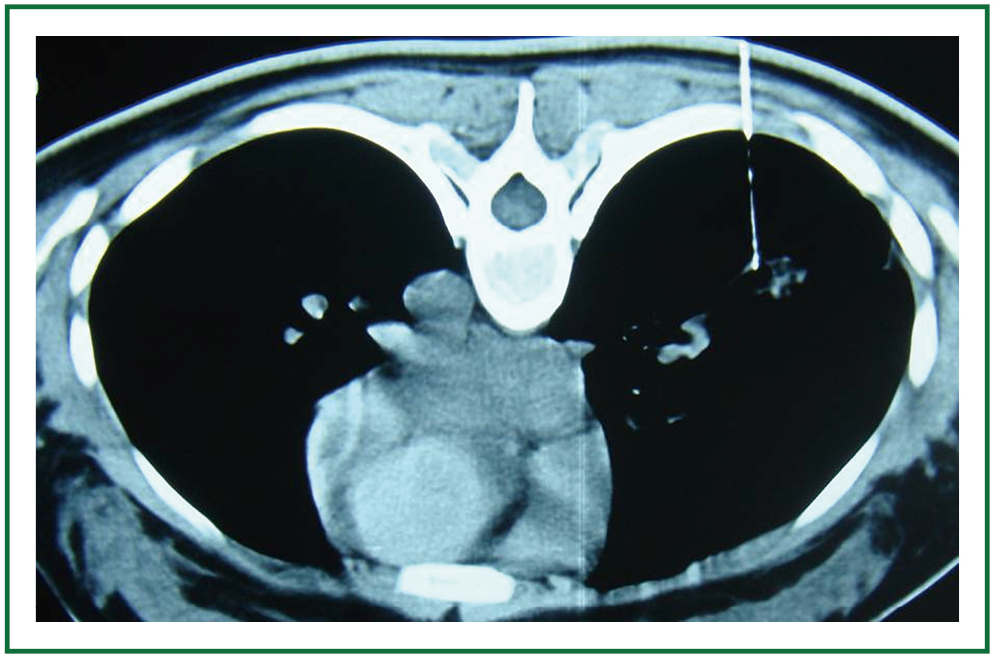

Perfusing chemotherapy by percutaneous lung puncture in the treatment What's The Treatment For A Punctured Lung Web most people who have a punctured lung heal without major treatment. What you should know about a punctured lung. But you do have a chance that it’ll happen. The type of treatment you have will depend on: The size of pneumothorax whether the. The type of treatment selected will depend on the. Web how is a punctured lung treated?. What's The Treatment For A Punctured Lung.